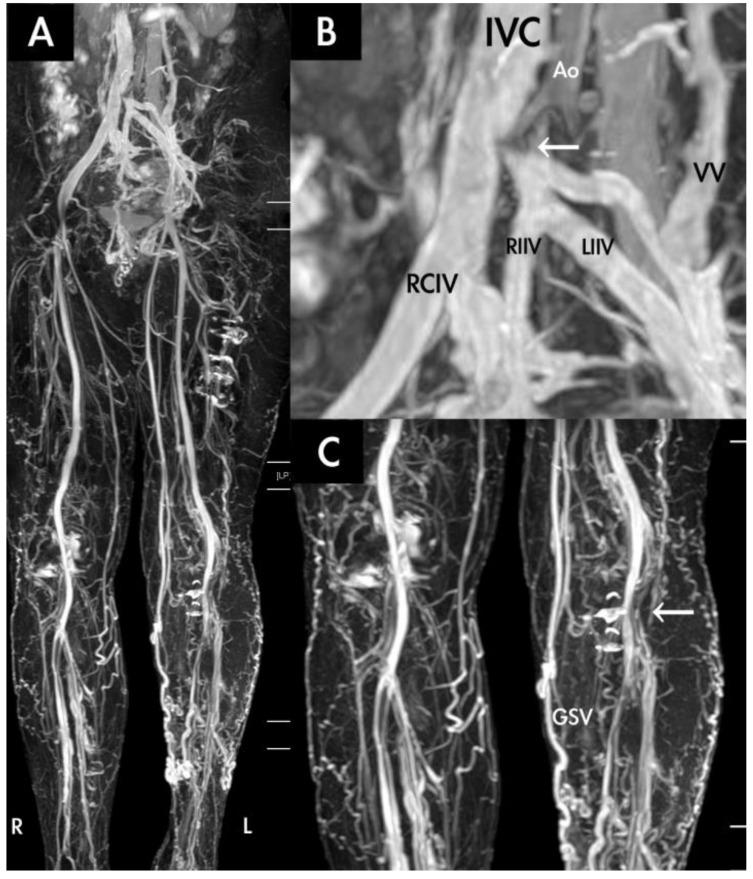

Between April 2017 and June 2019, 66 patients were evaluated for venous diseases through TRANCE-magnetic resonance imaging (MRI) and were grouped according to whether they had occlusive venous (OV) disease, a static venous ulcer (SU), or symptomatic varicose veins (VV). The clinical appliance of TRANCE-MRI was analysed by groups.

RESULTS

In total, 63 patients completed the study. TRANCE-MRI could identify venous thrombosis, including that of the abdominal and pelvic vessels, and it enabled the timely treatment of underlying diseases in patients with OV disease. TRANCE-MRI was statistically compared with the duplex scan, the gold standard to exclude deep vein thrombosis (DVT) in the legs, with regard to their abilities to detect venous thrombosis by using Cohen's kappa coefficient at a compatible value of 0.711. It could provide the occlusion degree of the peripheral artery for treating an SU. Finally, TRANCE-MRI can be used to outline all collateral veins and occult thrombi before treating symptomatic or recurrent VV to ensure a perfect surgical plan and to avoid complications.

2017年4月至2019年6月期间,66例患者通过TRANCE磁共振成像(MRI)评估静脉疾病,并根据是否患有闭塞性静脉(OV)疾病、静态静脉溃疡(SU)或有症状的静脉曲张(VV)进行分组。对TRANCE-MRI的临床应用进行分组分析。

结果

共有63例患者完成研究。TRANCE-MRI能够识别静脉血栓形成,包括腹部和盆腔血管的血栓形成,并能及时治疗OV疾病患者的基础疾病。将TRANCE-MRI与双功扫描(排除腿部深静脉血栓形成(DVT)的金标准)在检测静脉血栓形成能力方面进行统计学比较,使用Cohen's kappa系数,其兼容值为0.711。它可以为治疗SU提供外周动脉的闭塞程度。最后,在治疗有症状或复发性VV之前,TRANCE-MRI可用于勾勒所有侧支静脉和隐匿性血栓,以确保完美的手术方案并避免并发症。